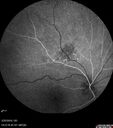

Amelanotic Nevus - OCT findings

60 year old man with normal vision. Nevus is 1 mm tall and was stable over 6 years follow-up

Amelanotic Choroidal Nevus352 views60 year old man. Nevus is stable over 6 years. Images are Photo, FAF, OCT, FA, ICG, and B-Scan     (0 votes)